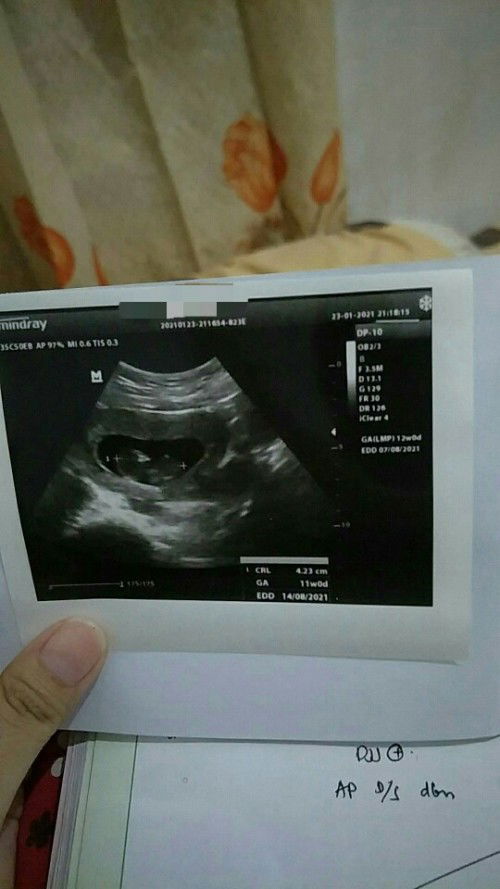

Hai bund, apa kabar? Setalh menanti berminggu2 untuk bisa lihat janinku akhirnya kmren malam kelihatan juga bund meskipun engga jelas, lumayan drpd yg pertama cuma lihat kantungnya aja. Emang beda ya bund hitungan hpl sma hitungan di usg, seharusnya sih udh 12weeks, tp di usg masih 11weeks.. Krna ini hamil pertama dan masih awam banget jujur dr kmren sempat kepikiran yang engga² krn perut masih rata, terus gak ada keluhan apa², sempat mikir ini janinnya beneran ada apa engga?? Kok ngga kerasa apa²? Akhirnya tes lab sekalian usg dan konsul dokter jawabannya "ada, dan memang normal di usia segini, malah bagus kalo gak ada keluhan ga rewel sama sekali" Rasanya..ah..lega👍 Jadi buat bunda2 yang usia kandungannya sma kyk aku jangan khawatir sma perut kecil krna janinnya emang masih "4 cm an" kecil banget kan. Semoga semuanya sehat dan lancar sampai hari persalinan dan seterusnya.. Aamiin!!! #bantusharing #firstbaby #1stimemom